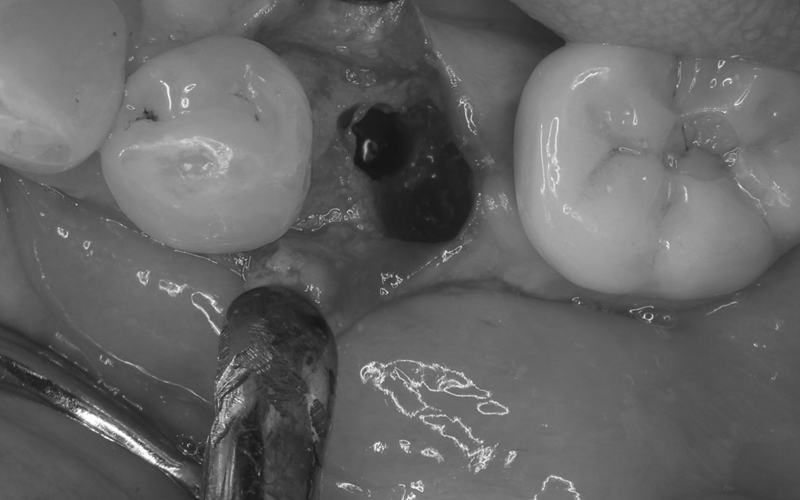

Case7

術前

術中

術後

| 治療名 | 抜歯即時インプラントとソケットリフトによる上顎臼歯部の修復症例 |

|---|---|

| 治療説明 |

歯の根が破折していたため抜歯が必要となり、患者さんとご相談のうえ、インプラントによる治療を選択しました。 ただし、インプラントを支える骨の高さが不足していたため、**上顎洞に骨を足す“ソケットリフト”**を併用し、安全にインプラントを埋入しました。 |

| 治療回数・期間 | 約3ヶ月 |

| 副作用とリスク |

・入れ歯や従来のブリッジと比べて、治療期間が長くなる傾向があります。 |

| 料金(税込) | 小規模GBR:110,000円 ソケットリフト:165,000円 インプラント一次手術:220,000円 二次手術:55,000円 上部構造〈セラミック〉:165,000円 合計:715,000円 |